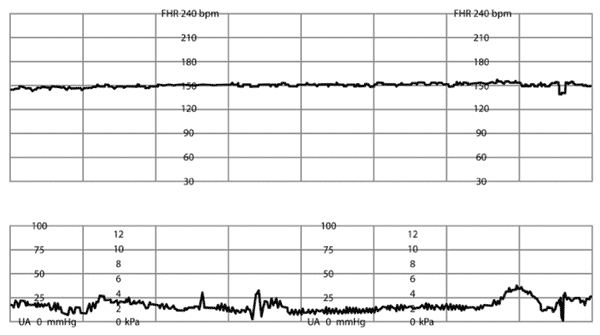

임신 36주에 접어든 28세 초산모가 태동 감소를 호소하며 내원했다. 혈압은 142/90mmHg, 맥박은 82회/분, 호흡은 20회/분, 체온은 36.7℃로 측정되었다. 초음파 검사 결과, 태아는 두위로 위치하고 있으며 예측 태아 몸무게는 1,700g (3백분위수)으로 나타났고, 양수지수는 5.5cm로 측정되었다. 골반 검사에서는 자궁경부가 닫혀 있으며, 소실은 관찰되지 않았다. 비수축검사와 탯줄동맥도플러검사 결과이다. 가장 적절한 처치 방법은 무엇인가?

[비수축검사]

• NST 상 loss of variability가 관찰되어 심각한 태아곤란을 시사하므로 응급제왕절개술을 시행한다.